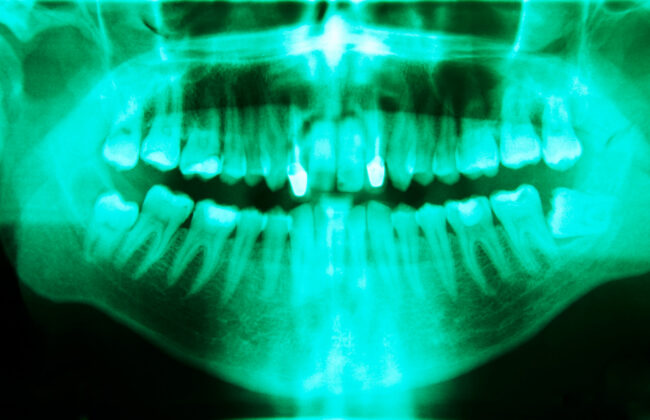

Wisdom Teeth Removal in Bixby: Safe, Smooth & Stress-Free Surgery If there’s one dental “milestone” nearly every teenager faces, it’s getting their wisdom teeth pulled. As a parent in Bixby, you want this rite of passage to be as easy and painless as possible for your son or daughter (and let’s be honest, for you too!). I’m Dr. Jeremy Egan, DMD, MD, and I’ve guided thousands of families through wisdom teeth removal with…